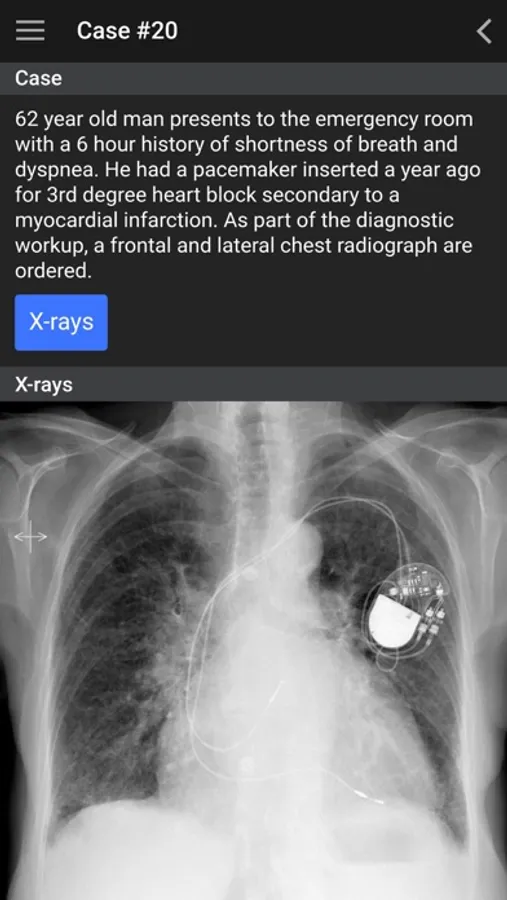

This app is designed for medical trainees and medical professionals to increase their confidence in identifying normal anatomic structures, ordering the most appropriate imaging test and identifying common pathology.

This app is based on the radiology undergraduate curriculum at the University of British Columbia (UBC), which is located in Vancouver, British Columbia, Canada. The app content is organized into the pre-clinical (MS1, MS2) and clinical (MS3, MS4, intern) years. The focus of the pre-clinical years is on identifying normal anatomy and acquiring basic ultrasound skills and the focus of the clinical years is to become familiar with ordering appropriateness criteria and to recognize key pathology. The list of clinical cases presented in this app are developed from the UBC third year medical student clerkship “Must See” clinical objectives.